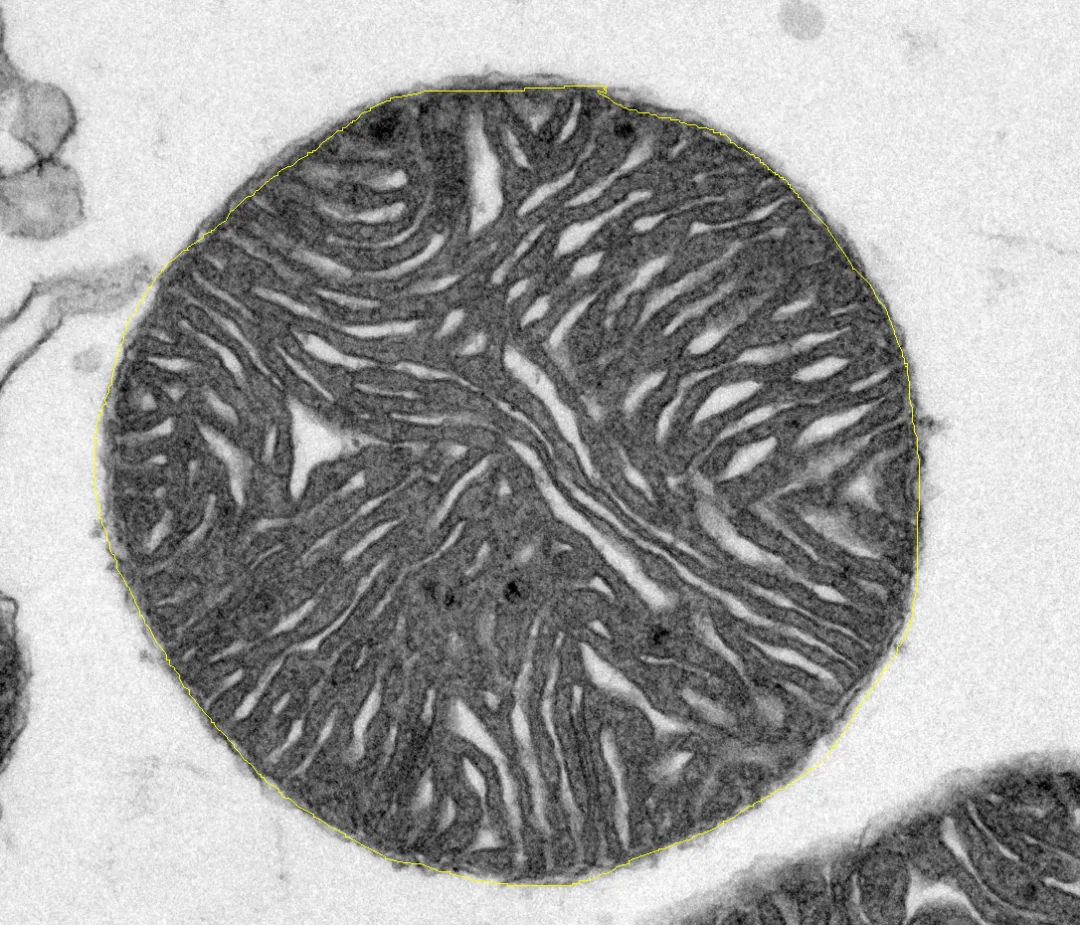

(2) 线粒体面积、周长、平均灰度值

Edit→Selection→Add to Manager,出现ROI Manager设置框→勾选Show All

软件主界面点击自由描线→对目标线粒体轮廓描线

点击Add则出现篮框内信息,即说明描线区域内信息已经加载

选中描线区域项目,点击Measure,计算结果,代表选中线粒体面积为2.023μm2,周长为5.152μm,平均灰度值为102.160(注意:灰度值范围为0至255,颜色越黑值越小,越白值越大)